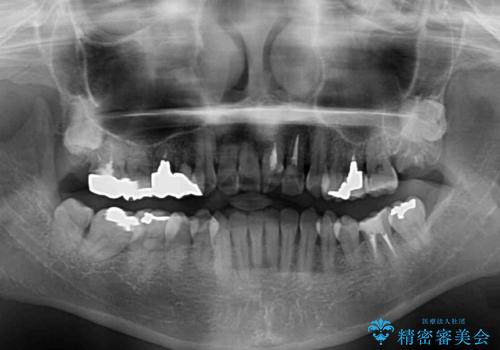

骨格的に下顎が前方位にありますが、歯列矯正で前歯の被蓋関係を改善することができると判断されたため、インビザラインにより矯正治療を行うこととしました。

また、上顎前歯と下顎大臼歯に神経を取り除いた歯があったため、矯正治療後に、セラミッククラウンにて補綴することとしました。

前歯が内側に倒れ込む力がかかり、正常な歯ぎしりもできないため、非常に負担のかかりやすい咬み合わせでした。